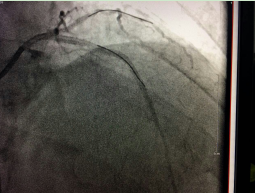

术前

三支血管严重钙化病变 患者主动要求实行微创介入治疗

入院后,经冠脉造影术检查显示,陈大爷的左主干及三支大血管(前降支、回旋支、右冠状动脉)都发生了弥漫性病变,尤其是左冠状动脉前降支、回旋支伴随着严重的钙化病变,最狭窄处堵塞达到95%;右冠状动脉也存在严重钙化病变,钙化物几乎将整个血管堵满,导致心肌缺血出现胸闷胸痛症状。